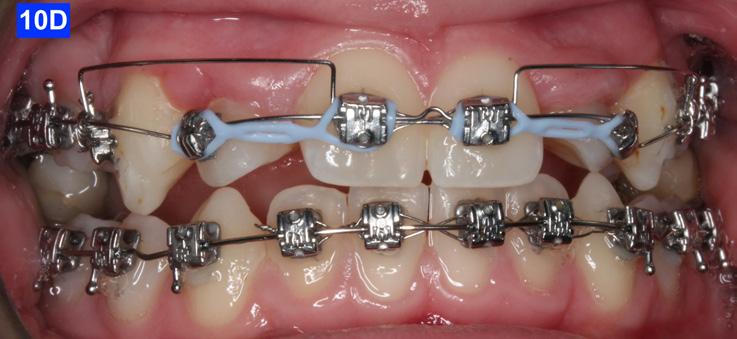

placed between the maxillary central incisors and the cuspids, on a .018 ss arch wire.8 The purpose of this center bend is to move the roots apart. A side effect of this center bend is that the crowns have a tendency to move together. Therefore, an OCS was placed between the maxillary central incisors and the cuspids. (Figure 10 – A, B)

After the maxillary cuspids were in contact with the second bicuspids, we had to ascertain that there was adequate width in the inter-radicular space. A center bend - “V” pointing gingivally was

To protract the maxillary lateral incisors into the arch, the bite was opened using composite build-ups on the mandibular first molars. The protraction was started with a .012 ligature tie, and the resiliency of the arch wire created the labial movement of the lateral incisors (Figure 10 - C).

Figure 8A: TADs in situ, frontal view 8B: TAD in situ, right lateral view 8C: TAD in situ, left lateral view 8D: Power arms Figure 9A: Maxilla, occlusal view 9B: Maxilla, occlusal view 9C: Maxilla, occlusal view Figure 9D: After the removal of the Hyrax, occlusal view Figure 10A: Center bend “V” pointing gingivally Figure 10B: OCS between the cuspids and the central incisors Figure 10C: Composite build-ups on the mandibular first molars Figure 10D: Adrian “U” bend spring

The final labial movement and de-rotation was done by the combined use of an Adrian “U” bend spring and an EC (a .016 SS and a .014 NiTi) (10 – D, E, F). When the maxillary lateral incisors settled in their proper site, the leveling of the maxillary arch was initiated. The progression of the arch wires was a .016 NiTi, a .0.18 NiTi, a .018 SS and the final arch wire, a .019 x .025 SS. There was only a .018 SS arch wire in the mandible. The remaining spaces were closed with a combination of the OCS, EC, and triangular elastics (1/4” – 4.5 oz) (Figure 11-A).